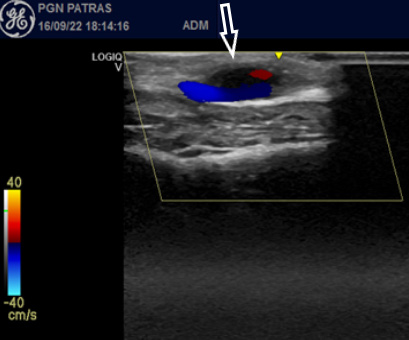

The third patient was an 18-year-old male who presented with a visible mass on his left temple (Figure 1). He had a motorcycle accident and received medical care for penetrating skin injuries on his forehead 20 days before. Five days later a

visible bulge appeared on his left temple, progressively enlarging.Physical examination revealed a painless, pulsatile temporal mass. Pulsation disappeared after proximal compression ofthe STA. A colour duplex confirmed the diagnosis of a STAP, measuring 1.4×1.1cm in diameter, while it also depicted the “to and fro” pattern and the “Yin-Yang sign” (Figure 2). The STA was ligated and the aneurysm was excised (Figure 3).

history and thorough physical examination are essential, confirmation of diagnosis is accomplished with imaging studies. Ultrasound (U/S) is the initial preferable technique due to its wide availability, noninvasiveness, cost-effectiveness, and its bedside applicability. Additionally, the superficial location of the STA enhances U/S resolution and moreover it may be easily used for follow-up5. U/S gray scale imaging is used to assess the pseudoaneurysm size and the intra-sac thrombus, while colour duplex is used to evaluate the neck and to locate the feeding artery. It displays the “to and fro” waveform in the neck and the colour flow inside the sac, known as the “Yin-Yang” sign (Figure 2). Computer Tomography Angiography (CTA) is usually the first imaging study in multi-trauma patients which may depict a coexistent STAP. Magnetic Resonance Angiography (MRA) and Digital Subtraction Angiography (DSA) have also been used4,6.